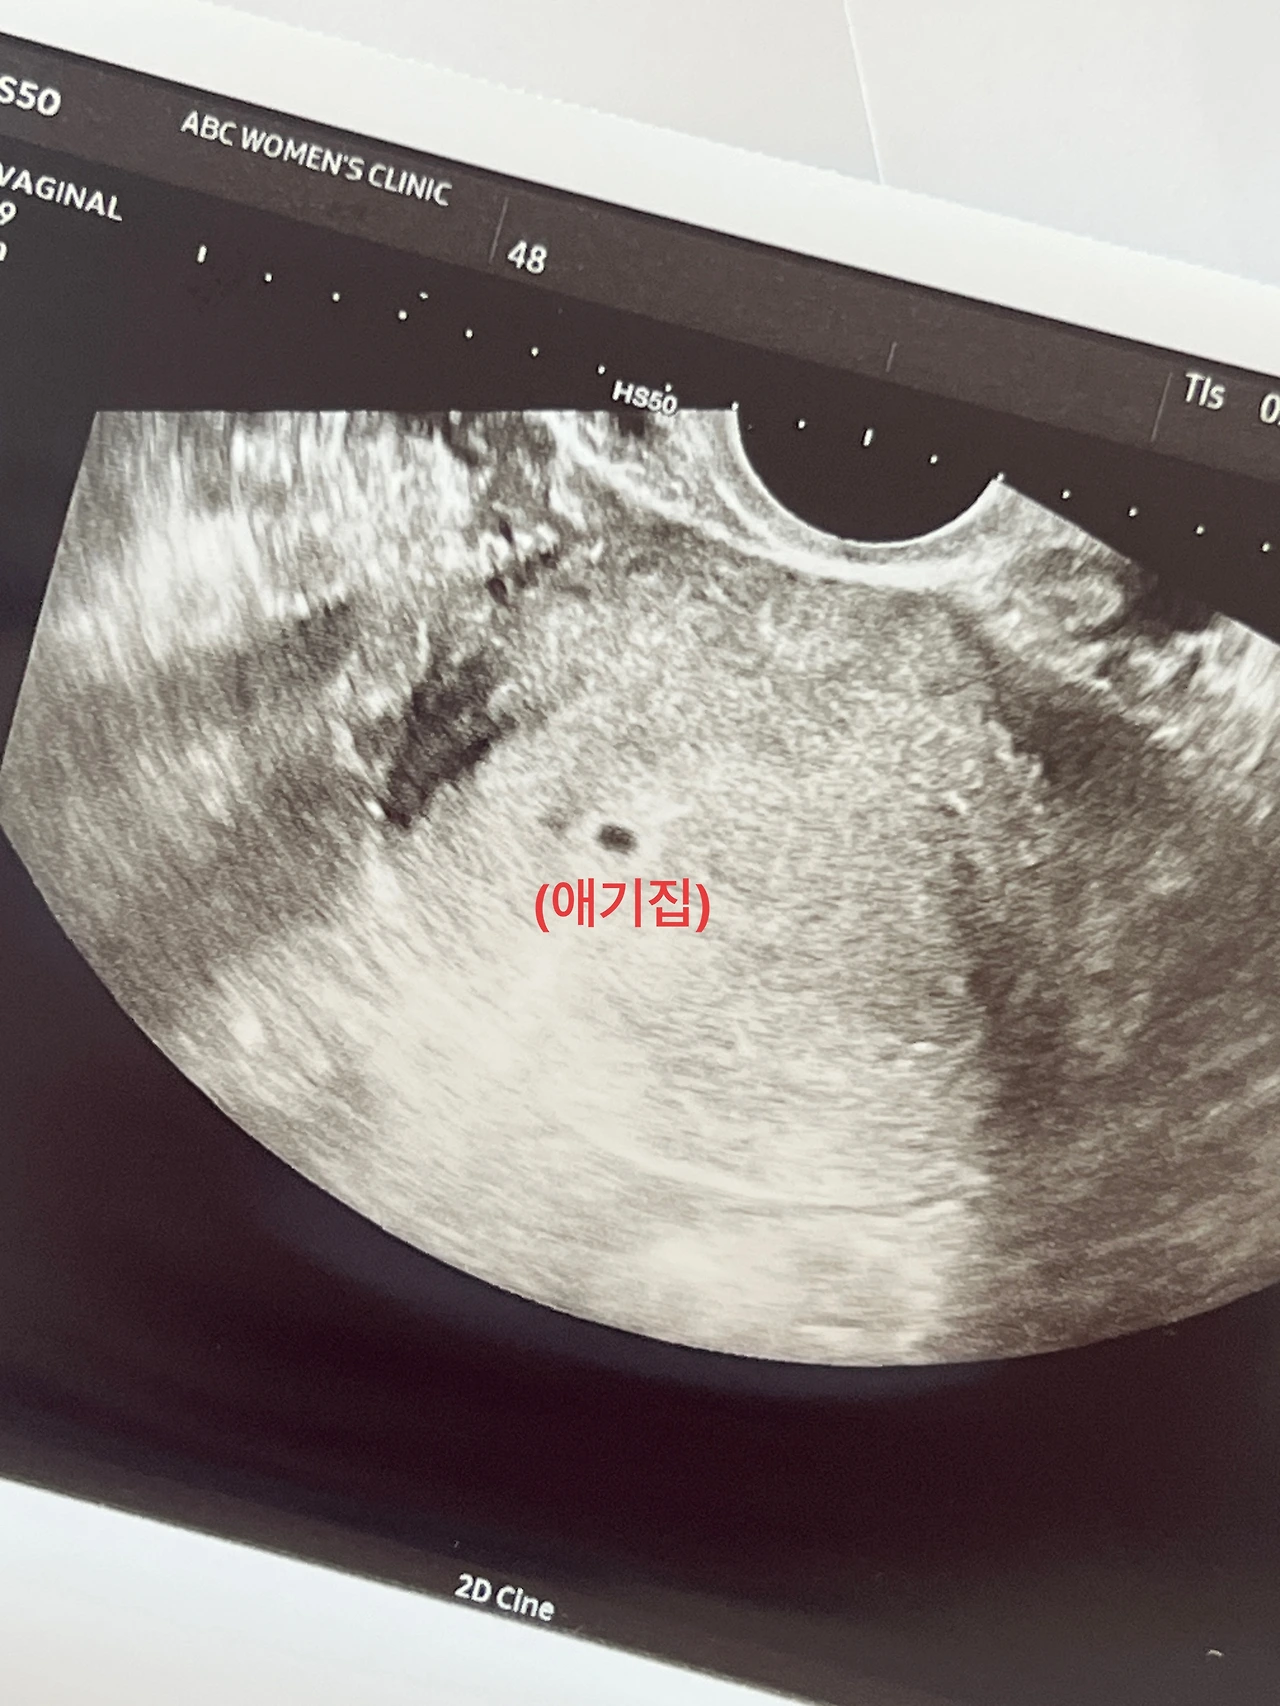

초음파 사진을 보니 후추 한 알을 닮은 0.6cm의 아주 작고 귀여운 아기집과, 그보다 더 작은 눈꼽만한 난황이 보였다. 착상 위치도 아주 괜찮다고 하셨다. 조그만 아기집과 난황을 보는데 너무 귀엽다는 생각이 들었다. 어떻게 위치도 딱 좋은 위치에 자리잡았는지 기특하기도 했다. 아기는 아직 너무 작아서 형체도 볼 수 없었는데, 다음 주에 오면 심장 소리를 들을 수 있다고 하셔서 깜짝 놀랐다. 진짜 빠르게 성장하는구나! 진료실에서 나와 남편에게 초음파 사진을 보여줬다. 내가 그렇듯 남편도 크게 실감이 나진 않아 보였지만, 왠지 남편의 얼굴에서는 기쁨과 신기함 그리고 약간의 미래에 대한 걱정이 느껴졌다. 가장의 무게를 제대로 느끼게 된 첫 순간이리라. 안내데스크 간호사님도 끝까지 친절하게 설명해 주시면서 축하한다고 해주셨다. 정말 첫 임신의 사실을 이 병원에서 알게 되어 천만 다행이라고 생각했다.